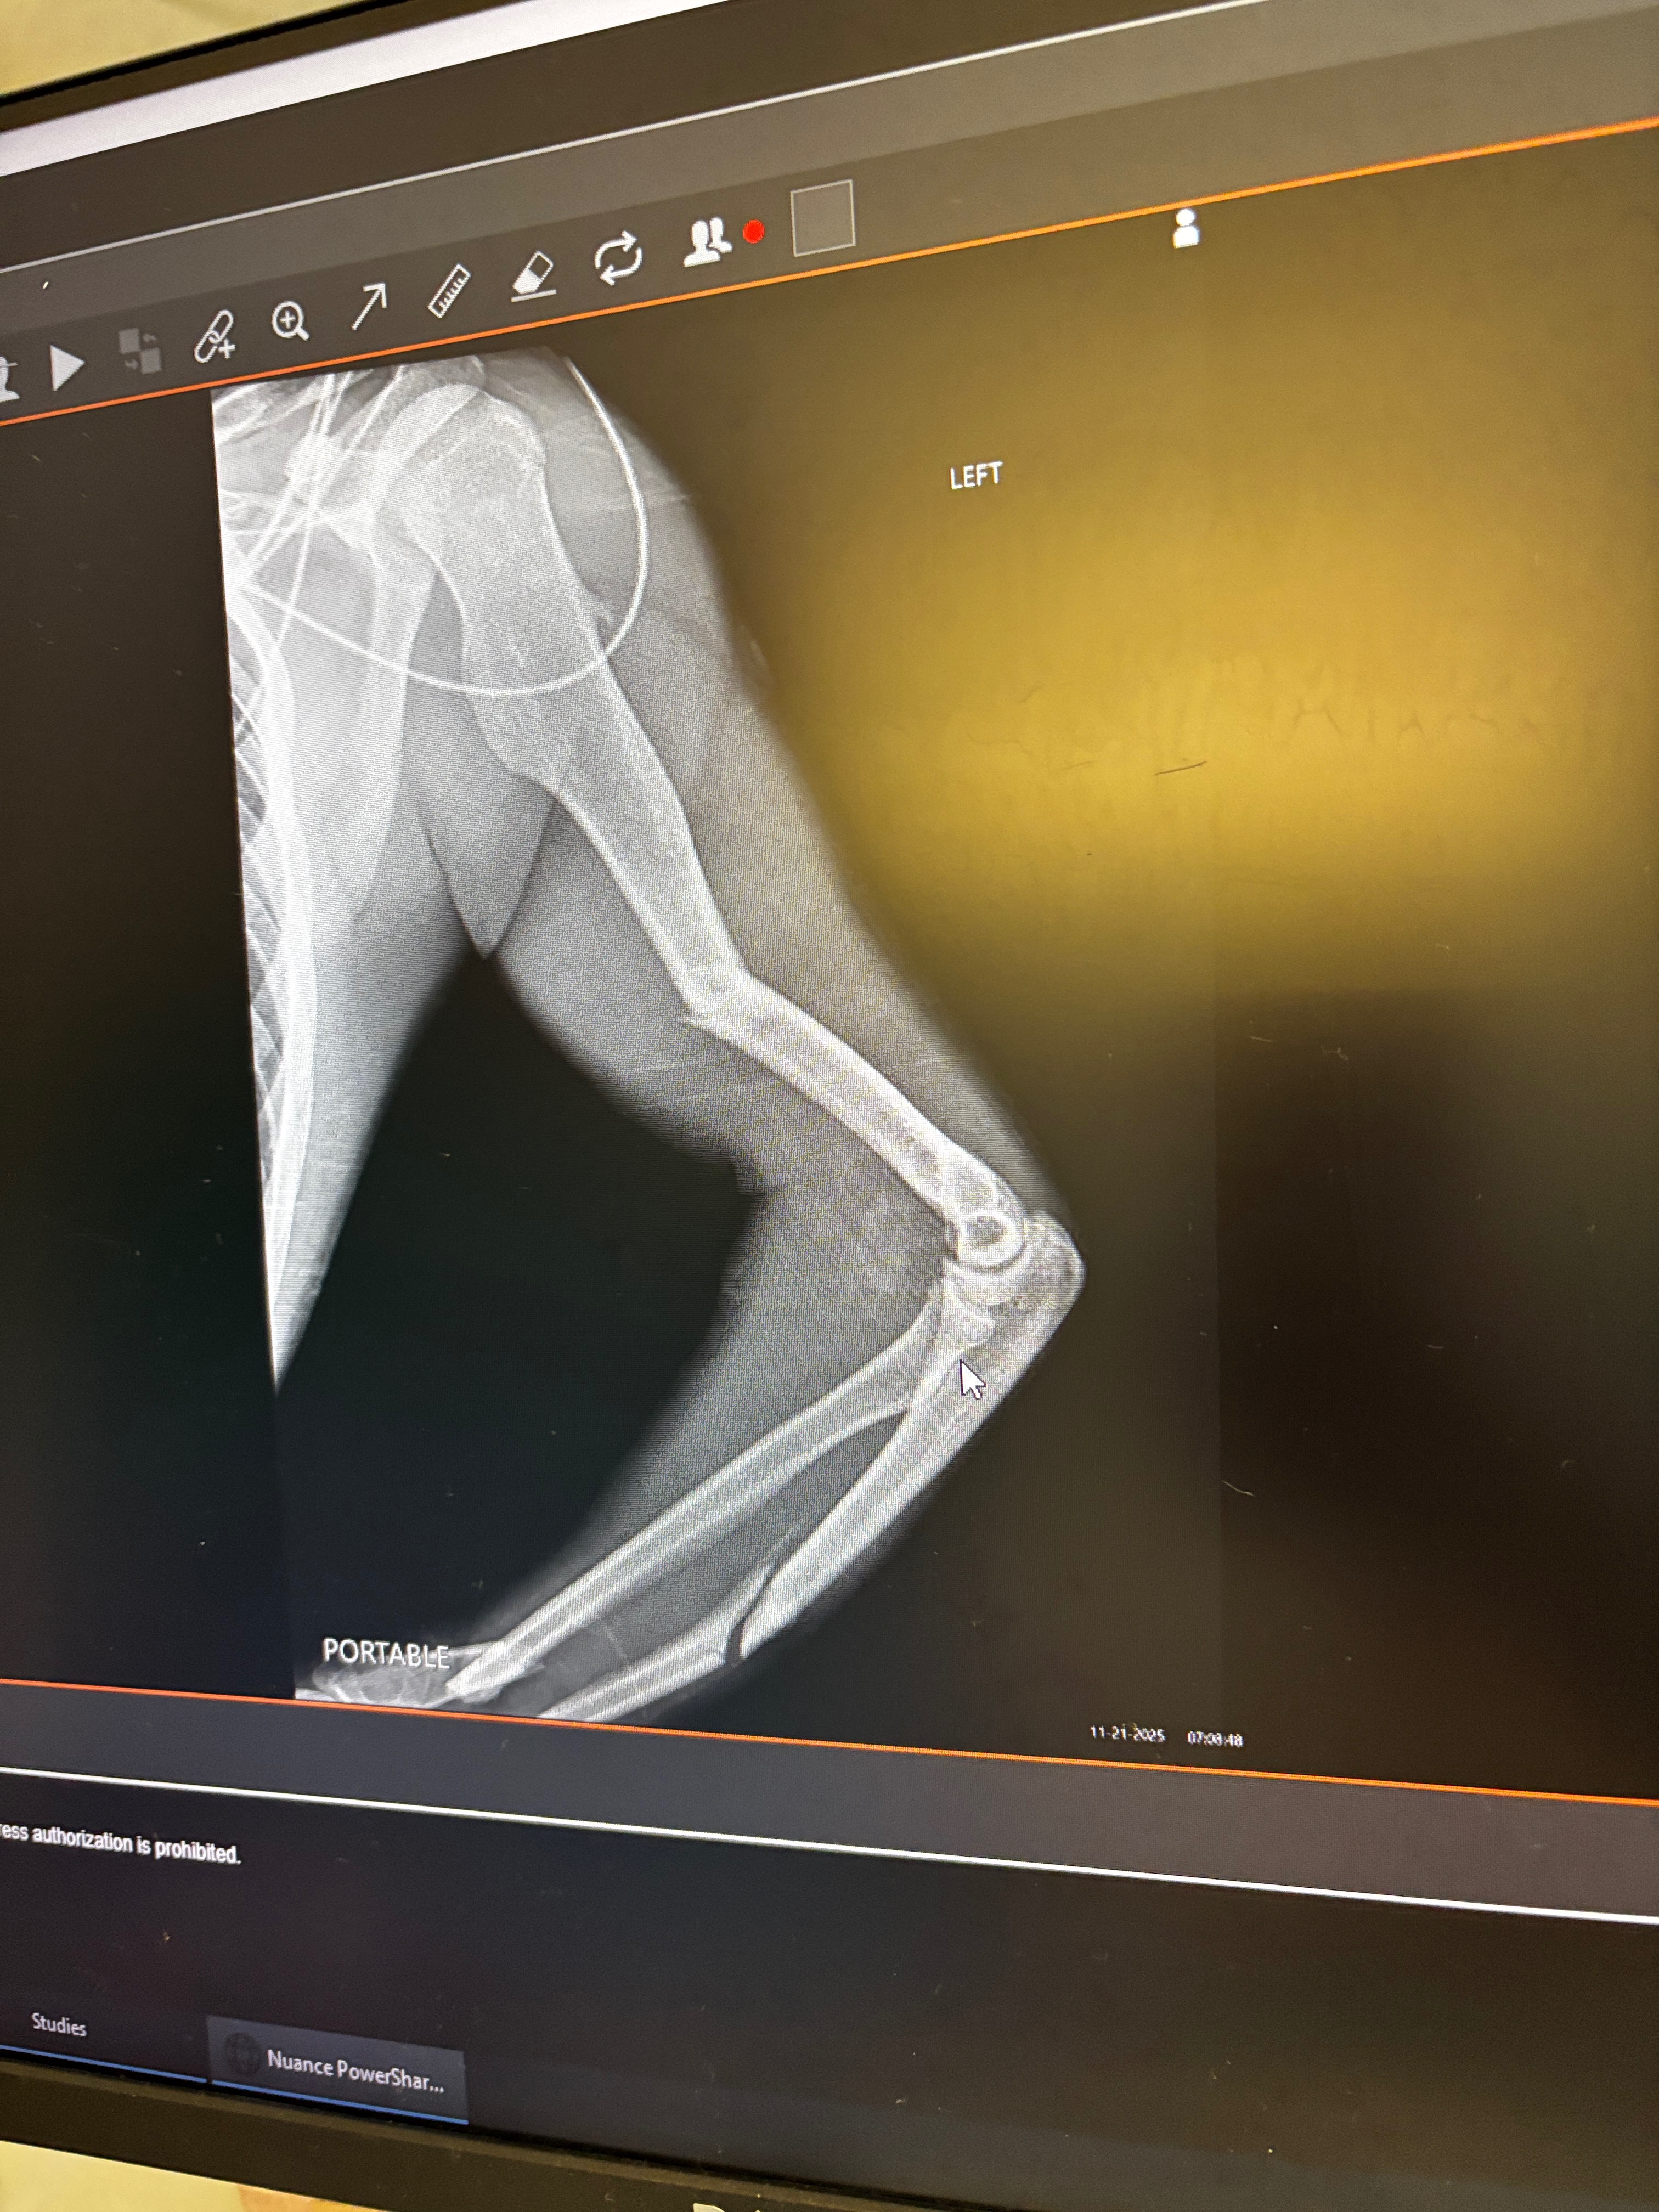

Thankfully, his boss saw and stopped the PTO. Peyton was rushed to the ER where he only spent about 40 minutes max. They did what they could and decided he needed to be sent almost 2 hours away to the best hospital in Maine to have intensive surgery immediately when he arrived. He broke almost his entire arm, and burned 8% of his arm, burning his sweatshirt to him as well. He broke his arm in four different places and had a metal disk put in.